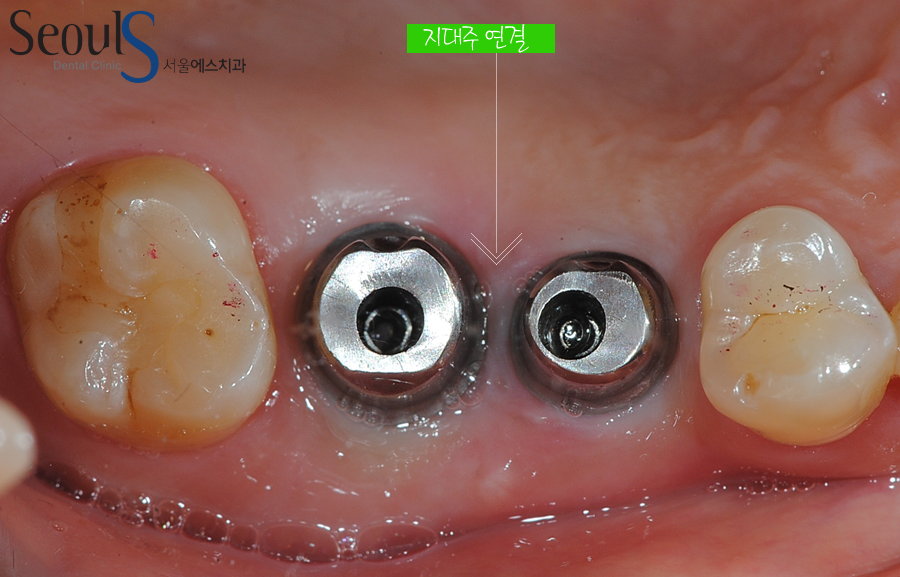

지대주 연결

임플란트와 잇몸뼈가 단단히 굳어 치아를 결합하기 위해 지대주를 연결한 모습입니다

지대주는 임플란트와 치아를 연결해주는 기둥으로

광진구 서울에스치과는 임플란트 지대주를 제작할 때

CAD/CAM 장비로 환자분 각각의 구강 상태에 적합한 맞춤 지대주를 제작합니다

지대주는 모양, 두께, 길이에 따라 시술 결과에 차이를 가져올 수 있고

환자분 각각의 잇몸 상태에 맞는 지대주를 제작할 경우

음식물 끼임, 임플란트 주위염을 예방할 수 있고 음식물 씹는 힘에 의해

보철물이 깨지는 것을 방지할 수 있습니다

저희 광진구 서울에스치과에서는 환자분 잇몸에 딱 맞는 지대주를 첨단 CAD/CAM 장비로 제작합니다